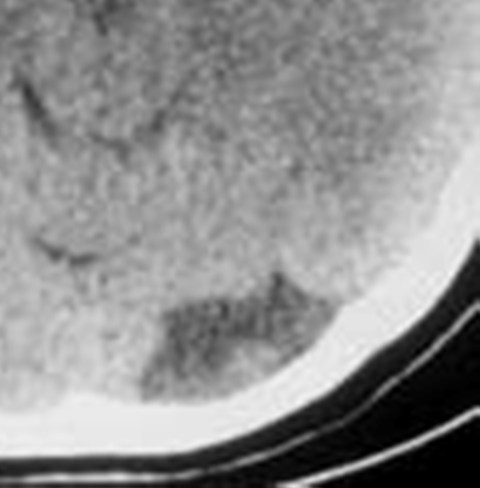

左侧枕叶脑软化灶?

支持 左侧枕叶脑软化灶?

作者: xulianj    时间: 2009-2-3 04:45

支持 左侧枕叶脑软化灶考虑。

双侧额叶脑梗塞,左侧枕叶脑软化灶,

支持 左侧枕叶脑软化灶考虑

作者: dengkai    时间: 2009-2-3 07:59

支持 左侧枕叶脑软化灶

支持考虑左侧枕叶脑软化灶。